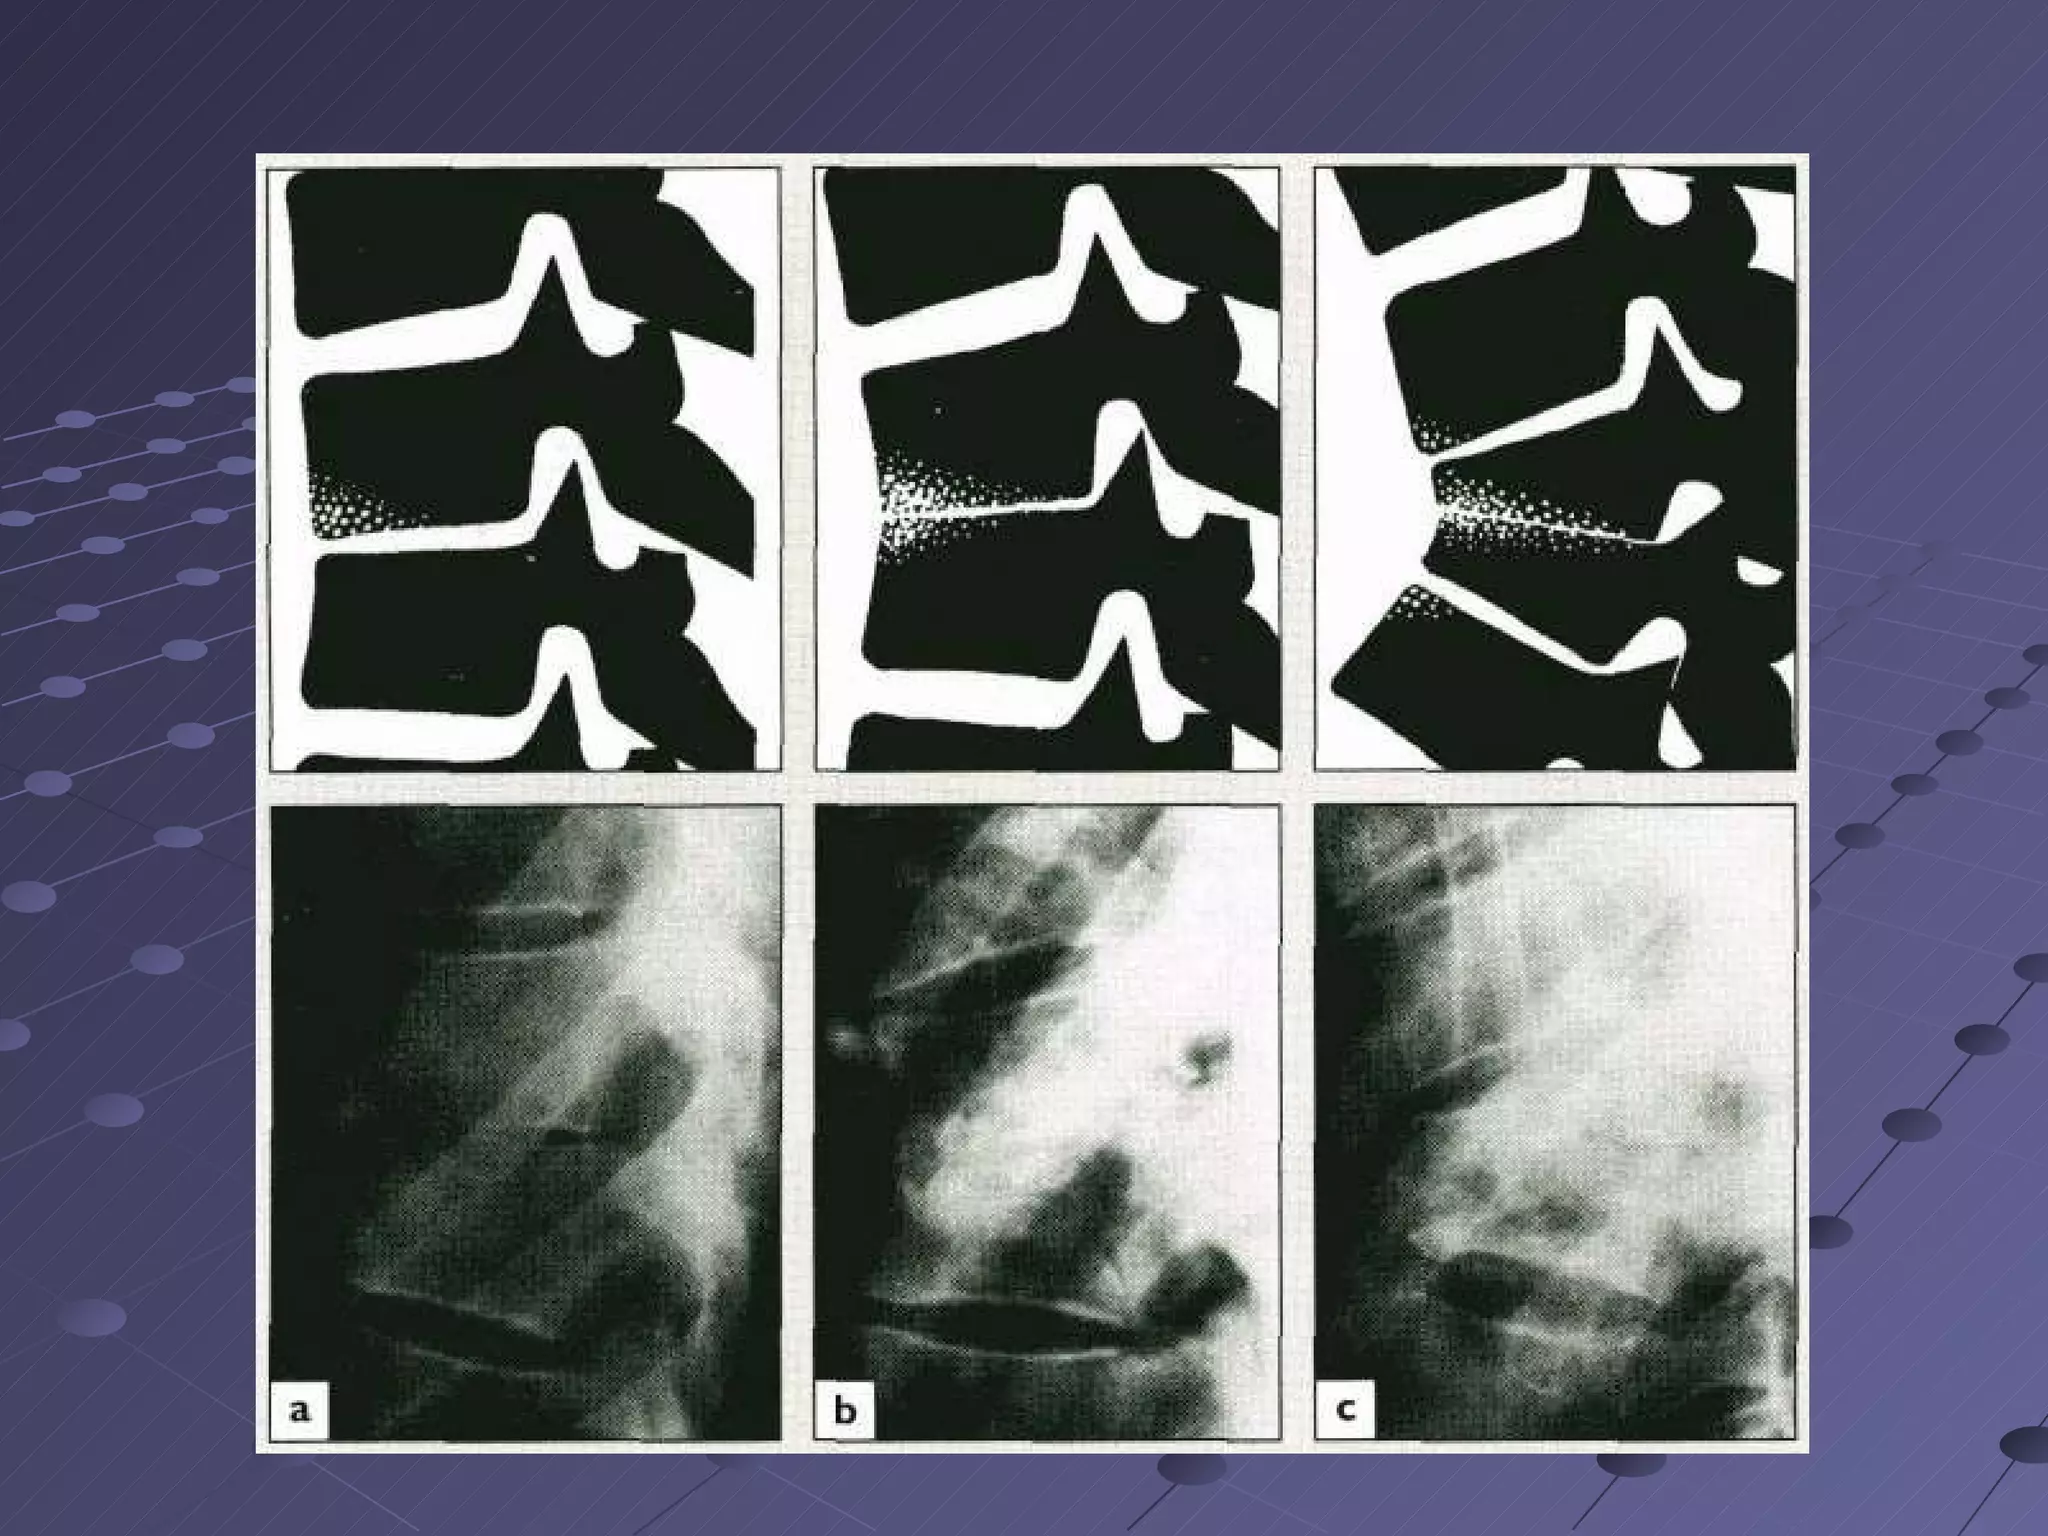

Imaging plain radiography …little value in early cases.  Disk-space narrowing and irregularity reactive new bone and occasionally paraspinal shadow. Radiographic changes are progressive with time but may remain limited to the disk complex. Plain radiographs are not very useful in assessing response to treatment.

loss of disc height, irregularity of the disc space , end-plate erosion and reactive sclerosis

X-ray   The entire spine should be x-rayed, because vertebrae distant from the obvious site may also be affected.  The earliest signs of infection are local osteoporosis of two adjacent vertebrae and narrowing of the intervertebral disc space Later an angular deformity of the spine.  Paraspinal soft-tissue shadows may be due either to oedema and swelling or to a paravertebral abscess…thoracic disease.  With healing paravertebral abscesses may calcify.

Early disease withloss of the disc space